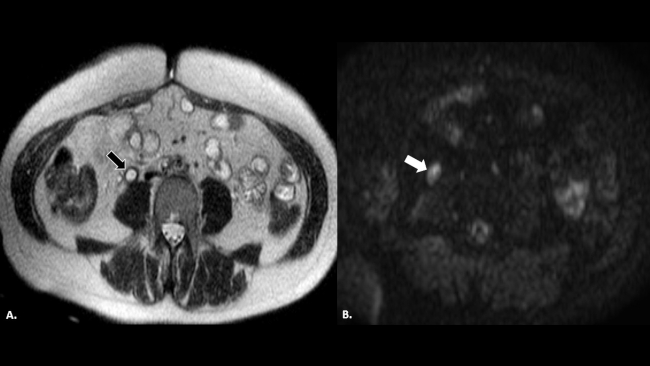

La RM (►Fig. 5) puede mostrar una mejor resolución espacial del cuadro inflamatorio en comparación con la ecografía, evidenciando un aumento en el calibre del uréter remanente, así como también el engrosamiento de sus paredes, la inflamación regional asociada con sus posibles causas y complicaciones. Raramente se utiliza la RM para certificar el cuadro diagnóstico, ya que no es tan ampliamente utilizada en urgencias abdominales y su detección por este método suele ser un hallazgo incidental.4,5,6,7,8

Paciente con nefrectomía derecha por implante pelviano secundario a un carcinoma de cérvix. (a) RM de abdomen en secuencia ponderada en T2, donde se reconoce uréter derecho dilatado, de paredes engrosadas con contenido líquido en su interior (flecha negra). En la secuencia en difusión del mismo paciente (b), se identifica inflamación del uréter remanente en secuencias de difusión (flecha blanca).